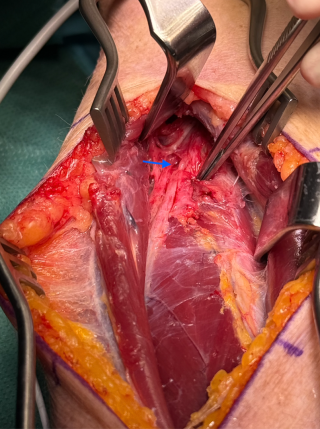

FM16

Recurrent PIN Palsy Following Neuralgic Amyotrophy Treated with Decompression and Nerve Transfer

Abstract

Sören Könneker1, Victor Sander1, Géraldine Lautenbach1, Simon Roner1, Olga Politikou1 (1University Hospital Zurich, Zürich)

Background:

Isolated palsy of the distal posterior interosseous nerve (PIN) is rare and may present spontaneously without clear etiology. Recurrence after initial recovery raises suspicion of neuralgic amyotrophy (Parsonage-Turner syndrome), particularly in the context of a post-infectious event. We present a unique case of recurrent PIN palsy managed successfully with decompression and selective nerve transfer.

Case Presentation:

A young woman presented with spontaneous paralysis of thumb extension (IP joint), retroversion, and abduction. Sonography showed no compressive pathology. Electroneuromyography (ENMG) demonstrated acute denervation of EPL, EPB, and APL, with pathological neurography of the PIN distal to the supinator canal. After 8 months of conservative treatment with hand therapy and no functional improvement, surgical decompression of the PIN in the supinator tunnel was performed. First signs of reinnervation appeared at 6 weeks, with full thumb ROM at 3 months.

One year later, following a flu-like illness, the patient developed progressive recurrence of thumb extension and abduction weakness, leading to complete paralysis within 6 months. Hand therapy failed. Sonography suggested possible compression, prompting surgical re-exploration. Intraoperatively, an hourglass deformity of the PIN distal to the supinator canal was identified. Given the nerve’s poor appearance and uncertain prognosis, a distal nerve transfer was performed: the distal anterior interosseous nerve (AIN) was coapted to the distal PIN through a dorsal approach via membrana interossea dissection, selectively reinnervating APL, EPB, and EPL.

Results:

At 9 months postoperatively, the patient achieved full extension of the thumb at the CMC, MCP, and IP joints. Strength remains at M3. No complications were observed.

Conclusion:

This case illustrates the potential for recurrence of spontaneous distal PIN palsy due to neuralgic amyotrophy, supported by post-viral onset and hourglass deformity findings. A combination of decompression and selective distal nerve transfers provided a favorable functional outcome and represents a viable surgical strategy in recurrent cases with limited regenerative potential.